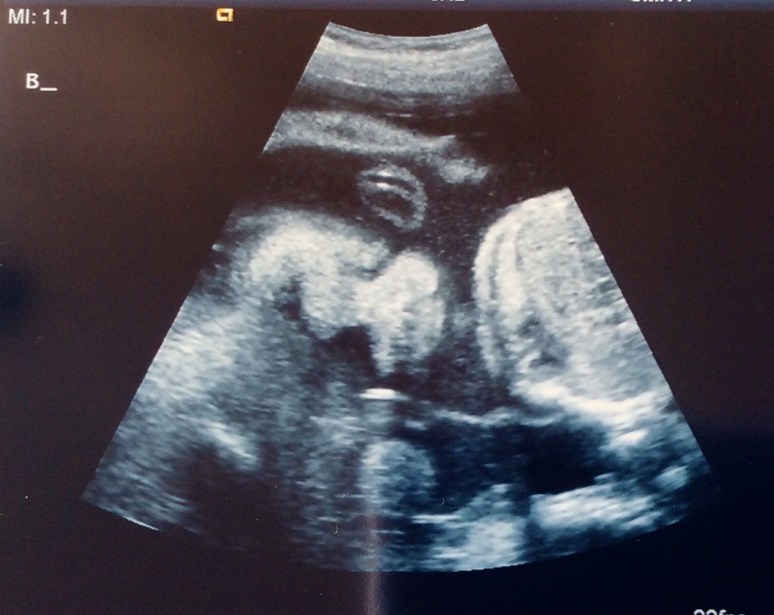

Monday we had our fetal echo and it looks like both babies hearts are just fine. Sigh of relief! Baby A still has her small calcification, but the radiologist was not concerned at all and said not to worry. We also had another growth check at this same ultrasound appointment. Baby A is estimated to be 1 lb 14 oz and Baby B is estimated to be 2 lbs. Baby A is in the 67th percentile and Baby B is in the 83rd percentile. They are growing and we couldn’t be happier!

Baby A in profile